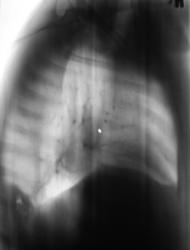

Пациент был направлен в рентгеновский кабинет терапевтом с диагнозом "Правостороняя пневмония". Было произведено стандартное исследование.

Было назначено противовоспалительное лечение. Через 1 неделю проведен "рентген-контроль".